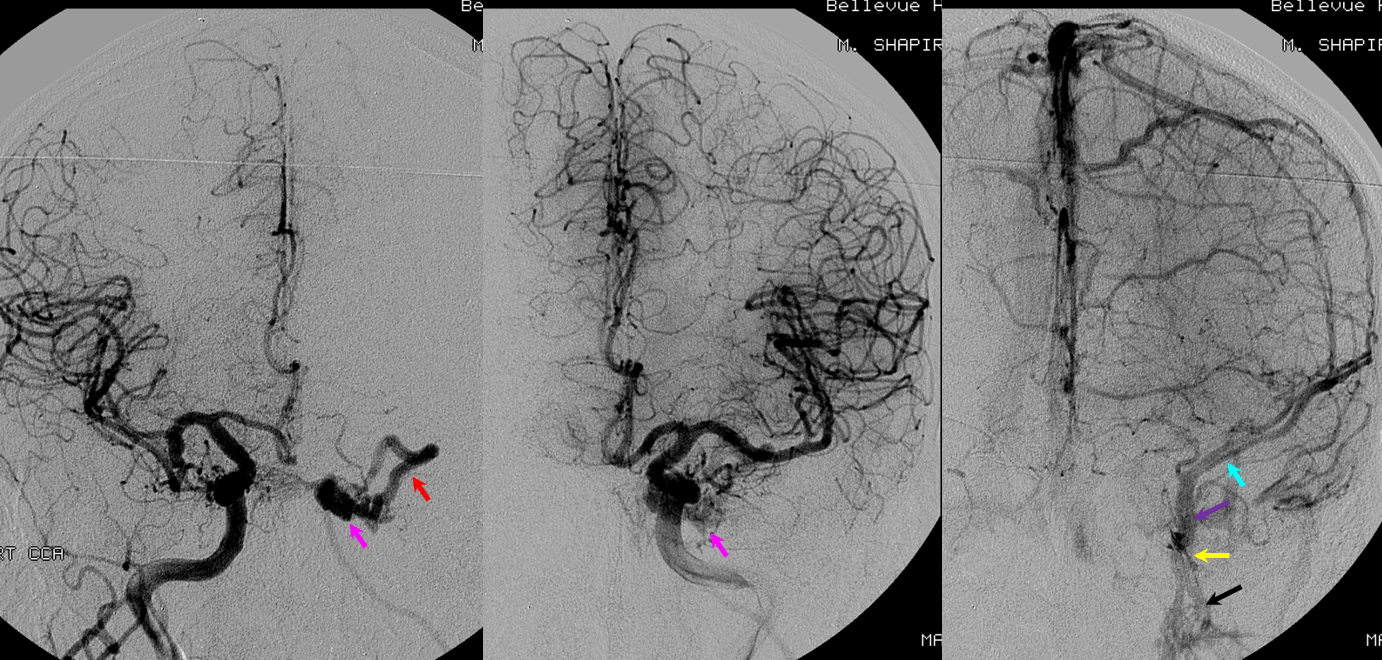

The superior sagittal sinus is a more variable structure than is generally assumed from straight-as-an-arrow diagrams. Although traditionally a single channel spanning the midline and terminating at the torcula, in practice you are likely to see additional dural channels, particularly in the posterior portion of the sinus, usually connecting with the transverse sinus system somewhat off midline. Often the sinus is deviated to the side, again over the occipital region. This is most noticeable on angio or stacked MIP images, as midline deviations when viewed sequentially on cross-sectional imaging are not as impressive. There is no particular clinical significance to this. But, it goes to show, as we emphasize in many places, that any part of dura can be a sinus. It does not have to be exactly where the falx joins. It does become important in surgical planning occasionally, and may play a role in evolution of sinus thrombosis cases (there are reports of “recanalization” of falcine sinus and other dural sinuses in patients with sagittal sinus thrombosis. Ultimately, these additional channels underline the evolution of dural sinuses, which are formed by coalescence of multiple channels, some of which can persist. In the patient below, the posterior portion of the SSS is particularly grotesque, with additional left (yellow) and right (pink) dural channels. The “true” SSS is in purple. The torcula is orange. Notice also a vein (green) which may appear like a dural sinus channel. However, it is only visualized from the left injection and is therefore unlikely to be a sinus.

Superior sagittal sinus angulation: It is extremely common to see the SSS angulated with respect to midline. Here, a small midline dural channel (blue) leads to the torcula proper (pink), while the “main” SSS (red) is deviated to the right. Which is the true torcula here is a matter of semantics; the important point is to recognize the arrangement.